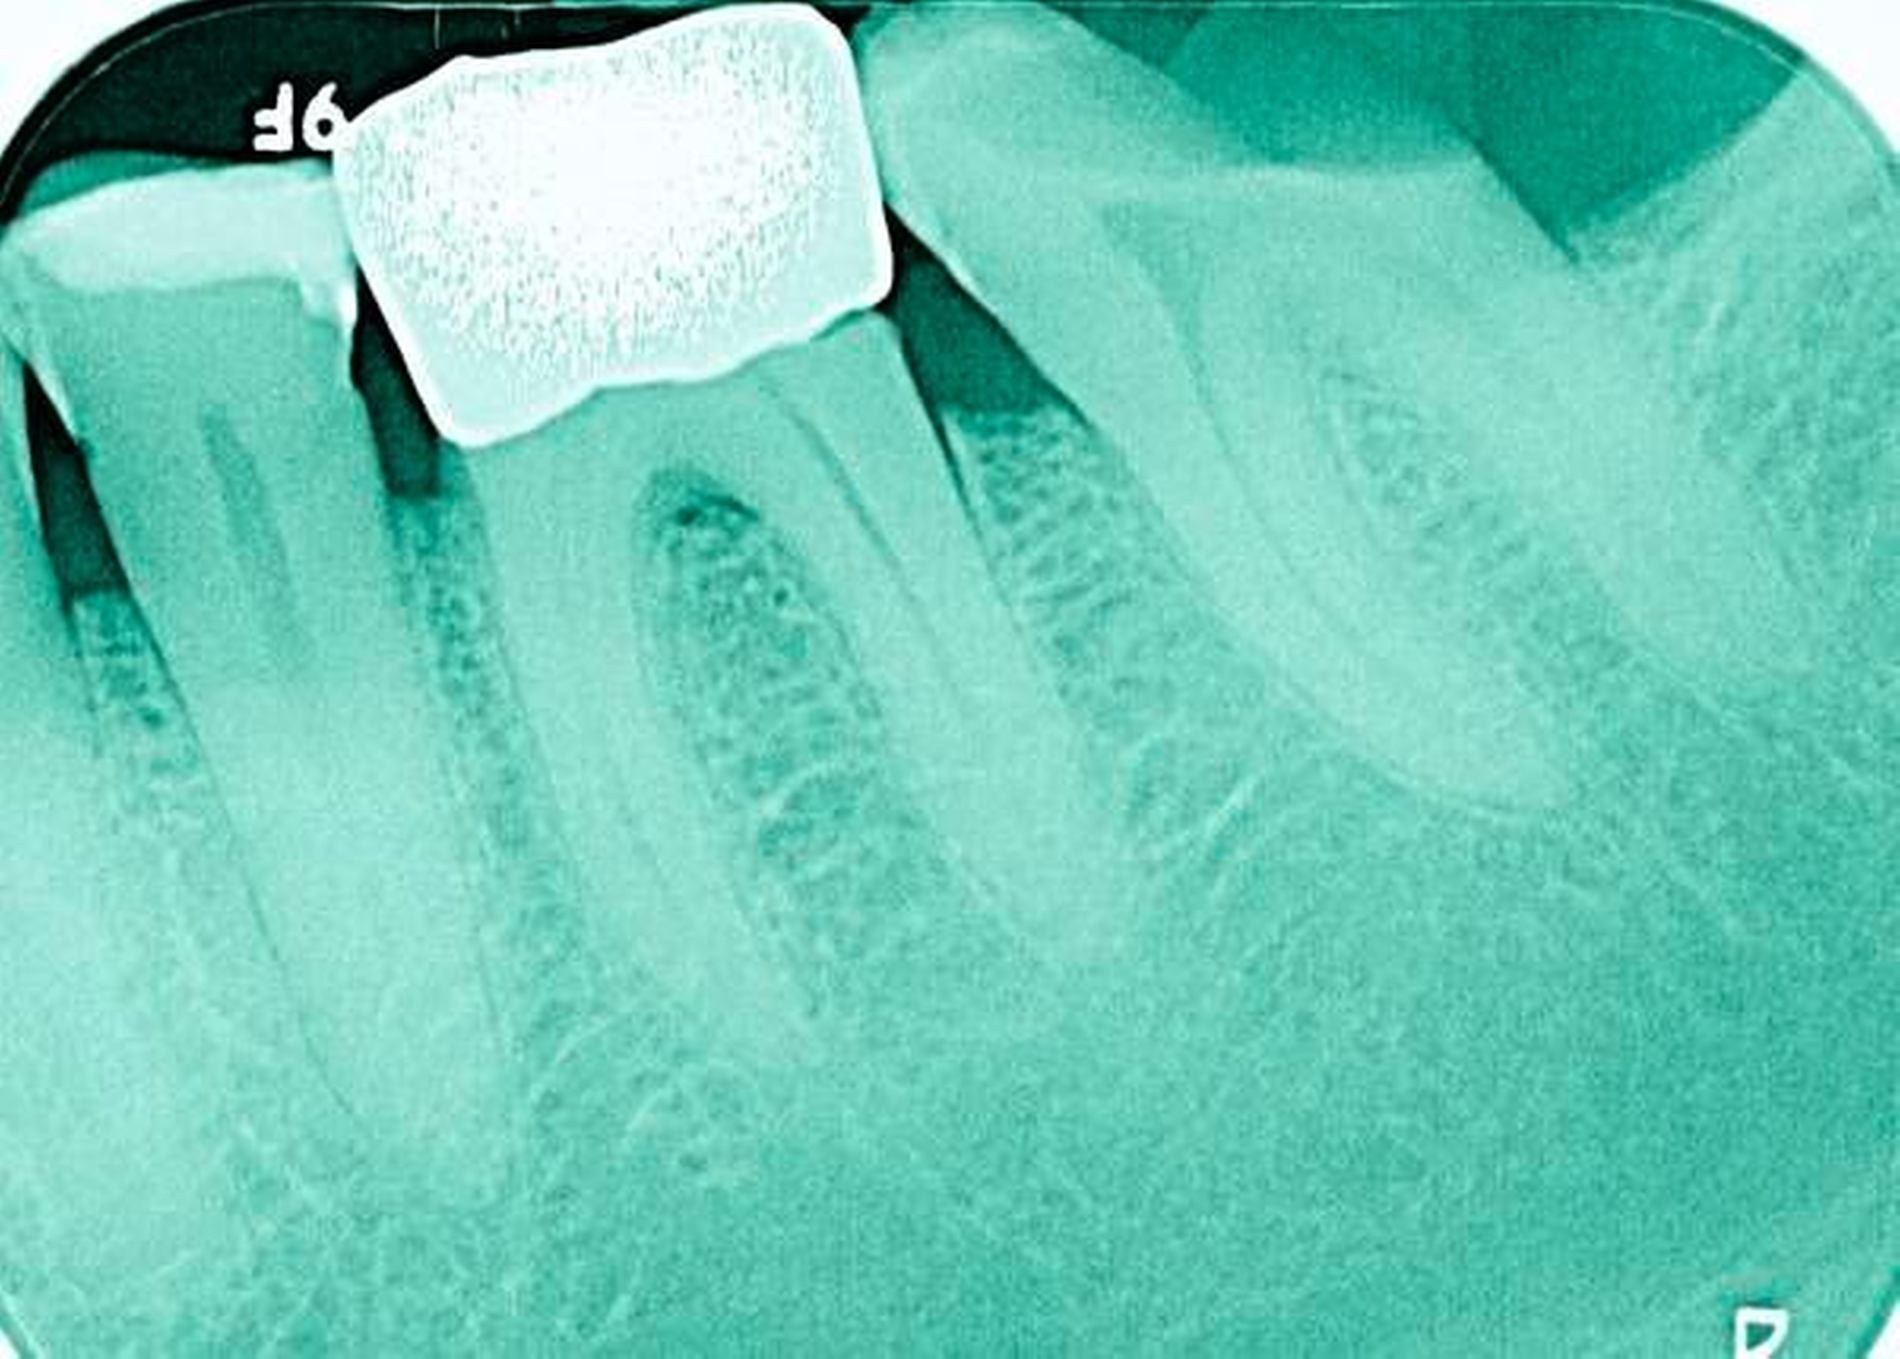

Abbildung 3: ausgedehnte Kronen- und Wurzelkaries unter einer Krone am Pfeilerzahn 47 einer seit Jahrzehnten eingegliederten Brücke von 45–47 bei einer 71-jährigen Patientin, die nach einer zerebrovaskulären Erkrankung unter Antikoagulantientherapie steht, vor etwa zwei Jahren hat sie eine Umstellung auf eine fluoridfreie Zahnpaste vorgenommen.

3. Restaurative Versorgungen bei Wurzelkaries

Freiliegende Wurzeloberflächen können im Alter ein locus minoris resistentiae für Karies sein. Im Zusammenspiel ungünstiger Ernährungsgewohnheiten, nachlassender Mundhygiene sowie Änderungen von Speichelquantität und -qualität kommt es zuweilen zu einem präventiv und restaurativ schwer beherrschbaren Auftreten von Wurzelkaries. Gut zugängliche Kariesläsionen können mit einphasig eingebrachtem Komposit (R1-Restaurationen) angegangen werden (Abbildungen 3 bis 5). Bei schwerer zugänglichen Arealen kommt ein zweiphasiges Vorgehen in Betracht (R2-Restaurationen). Das Vorgehen bei der R1- und bei der R2-Technik wurde mehrfach beschrieben [Frese et al., 2014a, b, c, d; Staehle et al., 2014, 2017]. Im Fall von zirkulärer Wurzelkaries sollte frühzeitig eingegriffen werden, da ansonsten die gesamte Zahnkrone frakturieren kann.